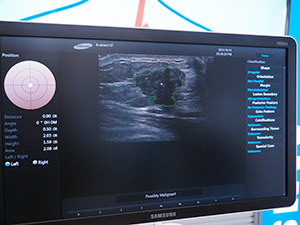

RS80Aは,新開発の高画質技術である“S-Vision Architecture”と“S-Vue Transducer”を採用した,同社がプレミアム超音波診断装置とうたう自信作。乳腺や腹部,循環器領域などに対応する。特に乳腺領域では,米国のBI-RADSのデータを用い,7800例の分析データから蓄積した情報を基に,腫瘍を自動的にトレース,抽出する機能“S-Detect”を搭載。自動抽出した情報をレポート出力することが可能である。また,エラストグラフィにも対応しており,乳腺領域では,“E-Breast”,甲状腺領域では“E-Thyroid”というアプリケーションを搭載している。

腫瘍を自動抽出するS-Detect |

この後,基調講演として,2講演が設けられた。まず,韓国サムスンメディカルセンター放射線科教授のKo Eunyoung氏が,「Initial Experience of S-Detect」をテーマに登壇した。Ko氏は,RS80Aの初期使用経験として,S-Detectでの腫瘍自動抽出が放射線科医の読影結果と91.2%一致しており,高い精度であると説明した。次いで「乳腺領域の超音波カテゴリー診断:BI-RADSとそのサポート機能S-Detectについて」をテーマに,亀田京橋クリニック診療部部長の戸﨑光宏氏が講演した。戸﨑氏は,BI-RADSについての解説を行った上で,S-Detectを使用した46症例の腫瘤性病変において,感度が90%,特異度が80.8%,正診率が84.8%であったとして,診断支援に有用であると報告した。